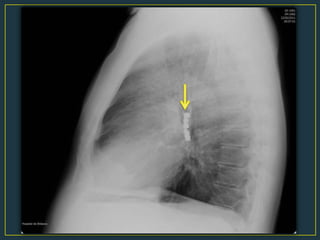

Rx de tórax : ¿anomalías estructurales?

• Enfisema lobar

• Anillo vascular

• Hernia diafragmática

• Etcétera…

• 14.

Rx de tórax: ¿anomalías estructurales? • Enfisema lobar • Anillo vascular • Hernia diafragmática • Etcétera…